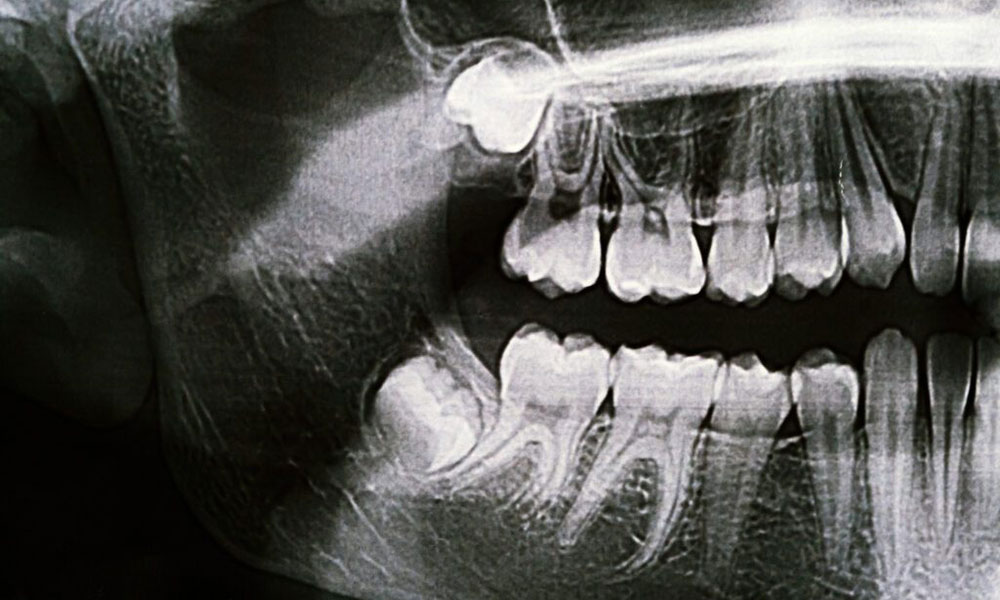

با استفاده از تصویر سهبعدی CBCT، پزشک مواردی مانند ضخامت استخوان، زاویه دندان و نزدیکی به عصب را بررسی میکند.

- استخوان کافی و سالم: تراکم و ارتفاع استخوان فک باید مناسب باشد.

- عدم آسیب به عصب یا سینوس: فاصله مناسب با ساختارهای حیاتی وجود داشته باشد.

- ریسک آسیب به عصب فک پایین (عصب آلوئولار تحتانی) بالاست.

- استخوان ناحیه دندان عقل معمولاً کمتراکم یا تحلیلرفته است.